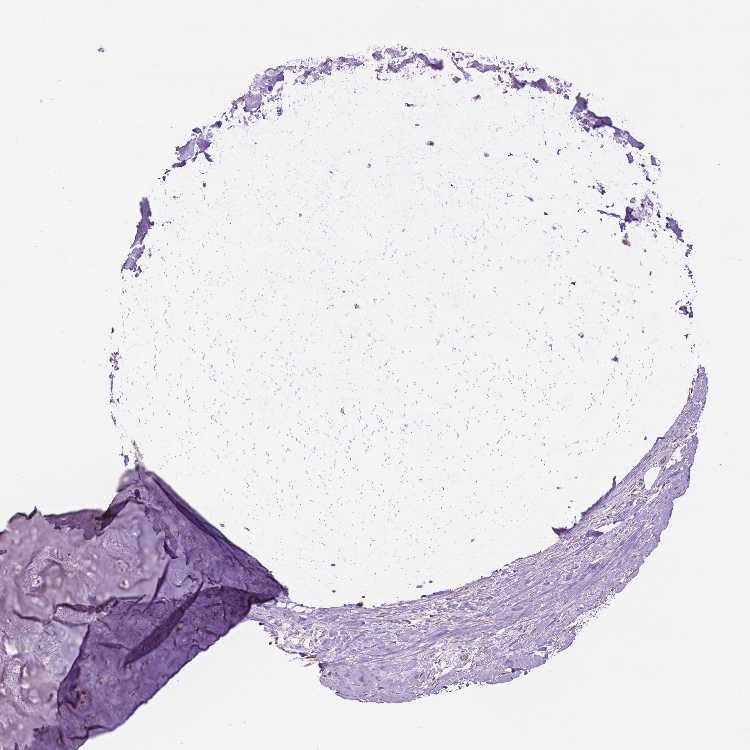

SOFT TISSUE 1 - Antibody stainingi

Antibody staining in the annotated cell types in the current human tissue is reported as not detected, low, medium, or high, based on conventional immunohistochemistry profiling in selected tissues. This score is based on the combination of the staining intensity and fraction of stained cells.

Each image is clickable and will lead to virtual microscopy that enables deeper exploration of all samples and also displays staining intensity scores, fraction scores and subcellular localization as well as patient and tissue information for each sample.

Antibody HPA035812

Chondrocytes Low

Fibroblasts Not detected

SOFT TISSUE 2 - Antibody stainingi

Fibroblasts Low

Peripheral nerve High